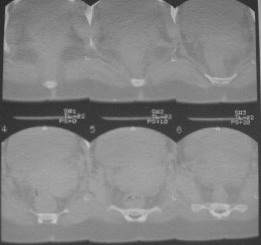

Из анамнеза: в ноябре 2002г. оступилась,упалана трап самолета (на верхней площадке, сразу при выходе из салона) на правый тазобедренный сустав, а затем - вниз на землю на ноги и ягодицы. Потеряла сознание от боли. Доставлена в больницу по месту жительства, лечилась консервативно с диагнозом кокцигодиния.На рентгенограмме от 27.11.02г. вывиха копчика не определяется (снимок идентичен представленной R-грамме от28.11.03г., кроме этого есть нормальная R-грамма копчика в боковой проекции).Через три недели стала ходить, но привести правую ногу в тазобедренном суставе не могла. Сейчас ходит отведя кнаружи правое бедро и голень, как ножку циркуля (фото 1). Неврологических нарушений нет. По просьбе врачаможет на 30-40 секунд поставить ноги вместе (фото 2). При этом испытывает сильную тянущую боль и ощущение "вывернутости" в правом тазобедренном суставе. Эти ощущения заставляют вновь отвести бедро. В положении лежа разогнуть бедро полностью не может из-за болей в ягодичной мышце (фото 3). Сгибание также ограничено из-за болей (фото 4). Отведение в положении лежа возможно в том же объеме, что и стоя (фото 5). Заподозрен старый разрыв правого крестцово-подвздошного сочленения.Выполнено R-исследование и КТ(в приложении). По-поводу деформации лонного сочленения выяснен гинекологический анамнез. Роды одни, нормальные в 22 года. Из роддома выписана на 8 сутки, нарушения походки не было, R-графия таза не проводилась. Вопросы на обсуждение: 1. Диагноз либо алгоритм дальнейшего обследования. 2. Лечебная тактика (в первую очередь возможность и целесообразность оперативного лечения).

Отсутствие изменений сустава на КТ и обычных рентгенограммах, стойкие боли и ограничение подвижности в суставе - симптомы, характерные для повреждения ацетабулярной губы. ЯМР с контрастом или без должны прояснить картину.

Уважаемый Юрий Алексеевич, сделаны ли пациентке более дистальные срезы КТ с захватом области тазобедренного сустава? Учитывая давность травмы, могли присоединиться и дистрофические процессы в субхондральной кости головки и впадины. Изменения в капсуле будут хорошо видны на УЗИ, особенно в сравнении со здоровой стороной. Эффективность лечебно-диагностического введения гормональных препаратов, на мой взгляд, сомнительна ввиду давности патологического состояния. При такой стойкой и давней контрактуре без операции вряд ли можно обойтись. Под наркозом амплитуда на разгибание должна увеличиться, усилить эффект можно тено-миотомиями заинтересованных групп мышц, капсулотомией + в послеоперационном периоде хорошее консервативное противовоспатлительное лечение с укладками на разгибание.Что мешает приведению пока не ясно, во встретившихся в нашей работе аналогичных ситуациях причиной был формирующийся медиальный остеофит головки, выталкивающий её из впадины.

эластичности этих мышц. В положении приведения происходит их перерастяжение, создается болевой синдром. На представленных снимках, к сожалению, эти структуры не определяются.